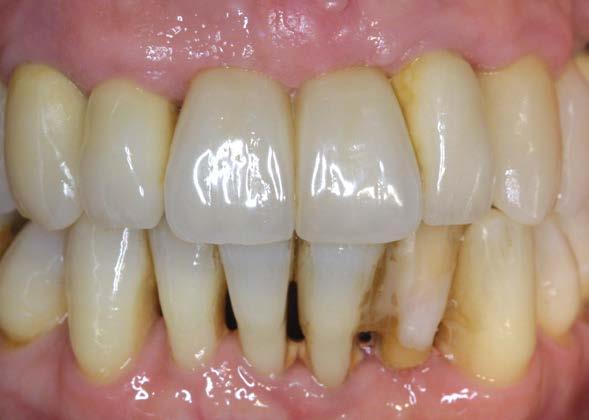

Un año más tarde, al finalizar el periodo de seguimiento (24 años), las fotografías intraorales evidenciaron ligeras alteraciones de los tejidos blandos, con pequeñas troneras abiertas,

más evidentes en los dientes naturales conservados que en las restauraciones implantosoportadas. A pesar de estos cambios, el resultado global se consideró satisfactorio desde el punto de vista funcional y estético, especialmente en comparación con la situación clínica y radiográfica inicial previa al tratamiento (Figuras 26–31).

Figuras 26–29. Imágenes clínicas a los 25 años. Se aprecia mínima pérdida ósea en dientes e implantes, con ligera apertura de troneras. Considerando el antecedente periodontal de la paciente, estos cambios pueden considerarse compatibles con una evolución controlada bajo mantenimiento estricto.